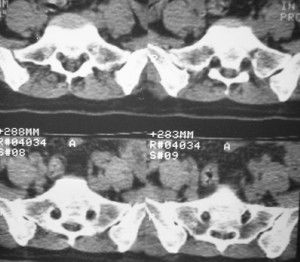

标题: CT7246: F,30岁,下腰痛,同事的片子,请老师们看看,初 [打印本页]

标题: CT7246: F,30岁,下腰痛,同事的片子,请老师们看看,初

典型的致密性髂骨炎

典型的双侧骶髂关节致密性骨炎.

何谓髂骨致密性骨炎?髂骨致密性骨炎是发生于髂骨耳状关节部分的骨质密度增高性疾病。病因迄今不明,可能与妊娠、机械性劳损、病灶性炎症有关。本病好发于20~35岁的育龄妇女,偶见男性。

髂骨致密性骨炎的临床表现与体征:腰骶部疼痛,多呈慢性、间歇性酸痛、隐痛,可向一侧或双侧臀部及大腿后侧扩散,但不沿坐骨神经方向放射,步行、站立、负重及劳累后加重,咳嗽、打喷嚏不能使疼痛明显加重,休息后症状减轻。患者腰骶角加大,局部有压痛和肌紧张,骨盆分离和挤压试验阳性,“4”字试验阳性,化验检查多在正常范围内。x线检查,骶髂关节间隙整齐清晰,靠近骶髂关节面中的髂骨耳状关节部分骨质密度增高,呈均匀浓白边缘清晰的骨质致密带,骨小梁消失,无骨质破坏。本病应注意与早期强直性脊柱炎、骶髂关节结核相鉴别。